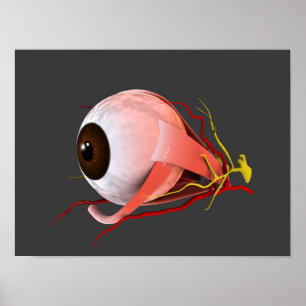

Impressão Em Tela Anatomia Do Olho Humano

Preço136,00 €